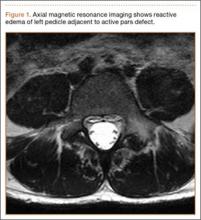

Diagnosis is crucial in early-stage lumbar spondylolysis, as osseous healing can occur with conservative treatment.11,12 High signal change (HSC) in the pedicle or pars interarticularis (Figure 1) on fluid-specific (T2) magnetic resonance imaging (MRI) sequences has been shown to be important in the diagnosis of early spondylolysis and, subsequently, a good predictor of bony healing.13,14 We conducted a study to determine the clinical and radiographic characteristics associated with the diagnosis of early or active spondylolysis.